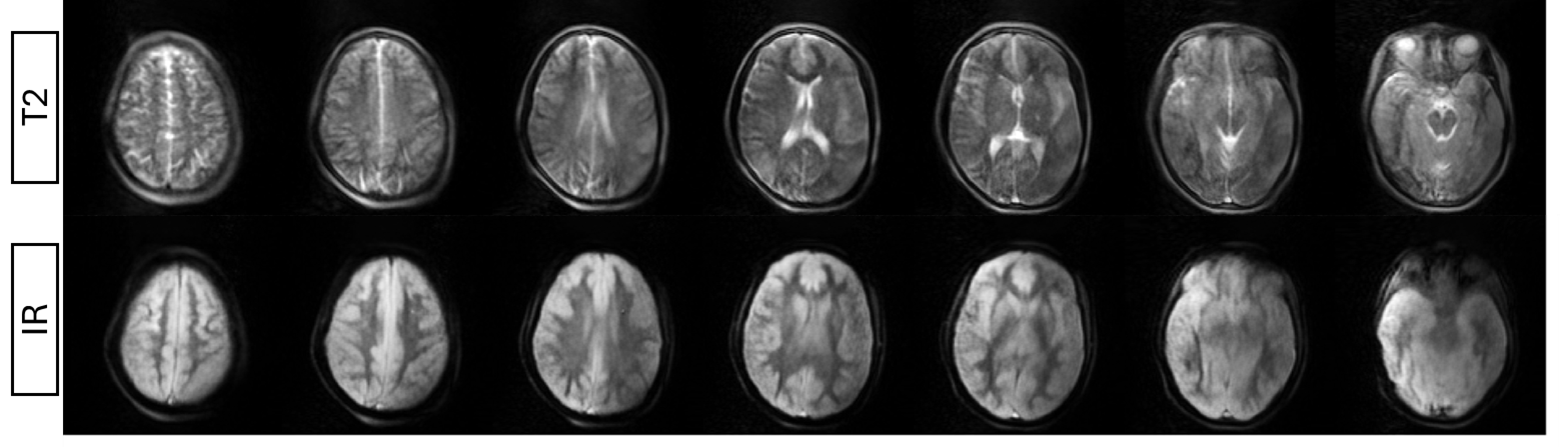

High Quality Images

Advanced technology delivers exceptional image clarity for accurate diagnosis from subtle injuries to complex anatomical structures, supporting precise clinical decision-making.

Imaging sequences include T1 RARE, T2 RARE, STIR RARE and RHO RARE all directed by a user interface. The equipment has a fully programmable Python environment.

A new generation of MRI scanners that operate with a low magnetic field (87 mT), are lightweight, portable and exploit efficient spatial coding schemes to enhance the diagnostic value of the resulting images, thus shifting the paradigm from highly sophisticated and expensive hardware to extremely efficient methods that balance rapidly growing healthcare costs worldwide. The elliptical bore of this new generation of MRI scanners allows imaging of the head and extremities.

Images made With Next MRI

With Next MRI you can investigate quickly and accurately, here we leave you some of the test images we have carried out.